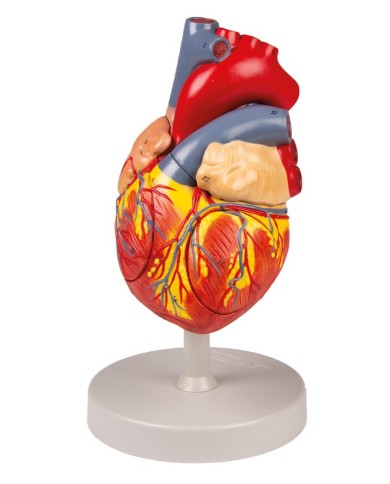

Fra i modelli di base segnaliamo il modello di cuore classico in due parti, in cui le due metà del cuore sono tenute insieme da potenti magneti.

Inoltre nella categoria sono presenti anche i modellini anatomici di cuore con bypass e con sistema di conduzione, fino ai modelli anatomici comparativi di patologie del cuore.

Per una migliore comprensione delle strutture anatomiche del cuore sono stati realizzati anche dei modelli anatomici di cuore ingrandito, si va dai piccoli ingrandimenti fino ai modelli di cuore per la formazione in aula, come il modello anatomico di cuore gigante prodotto da 3B Scientific: un modello di cuore ingrandito di ben otto volte.

Su Tuttoanatomia trovi la più vasta selezione online, certamente abbiamo il modello di cuore più adatto alle tue esigenze. I cardiologi e gli studenti acquistano i modelli anatomici di cuore umano per studiare nei minimi dettagli la struttura anatomica del cuore umano, ma anche per dare spiegazioni ai propri pazienti, per illustrare visivamente la patologia di cui sono affetti, ed il tipo di intervento che si intende eseguire durante la terapia. Le quotazioni su Tuttoanatomia sono le più convenienti del mercato e la qualità dei prodotti è davvero eccezionale, in modo da offrirti un rapporto qualità prezzo incomparabile.